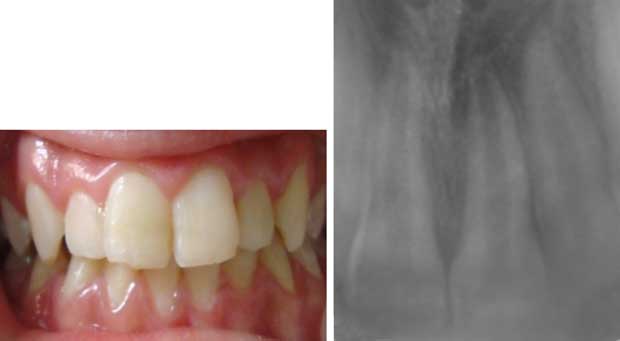

![]() Fig 13 : Contrôle clinique et radiographique à 10 mois après le collage.

|